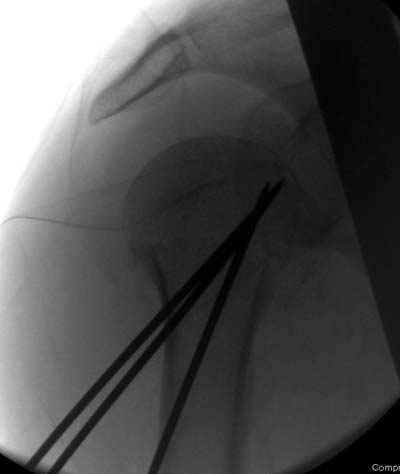

Сегодня взял больного повторно в операционную, не скажу, что повторная репозиция через неделю после первой попытки, была простая.

После удаления спиц попытался манипулировать отломками, но безуспешно, поэтому пришлось пользоваться периостальным элеватором, чтобы устранить смещение отломков и перепровести спицы. Проверил и перепроверил стабильность фиксации под ЭОПом, завтра Рг- будет готов, вот и поглядим....

Именно эти моменты+ дешевизна спиц и делают эту методику доступной практически в любых условиях (актуально для африканского государственного госпиталя). Хотя сейчас, пройдя через *подводные камни* понял , что для быстроты и простоты самой хирургии необходимо пользоваться drill sleeve and

wire guide, позволяющим ротировать пучок при его введении в головку (как объяснил Анатолий Ф.) Чтобы не терять время на поиск входного отверстия под мышцей удобно пользоваться drill sleeve 6,5 мм, удерживая его на кости после сверления отверстия, через него же провести и спицевой пучок, единственный момент который надо учитывать - чтобы размер петли не превышал диаметра протектора иначе придется начинать все сначала или в качестве альтернативы пользоваться разъёмными протекторами.

Что-то, наверно, сделали мы не совсем оптимально, поскольку у Анатолия Федровича и его соратников как-то красивее "раскрываются" спицы в головке плеча - надеюсь, он прокомментирует и подскажет, что надо подправить.